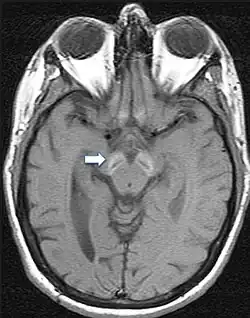

T1-gewichtete MRT-Aufnahme eines Gehirns eines Patienten, der an BPAN (Beta-Propeller-Protein-assoziierte Neurodegeneration) leidet. Sie zeigt einen hyperintensiven (hellen) Halo rund um ein gerades Band in der Substantia nigra und der Mittelhirnhaube (Pfeil). Dieser Halo ist ein diagnostisches Kennzeichen für BPAN.[9]

Da die Symptome meist unspezifisch sind, ist eine gesicherte Diagnose nur über bildgebende Verfahren und genetische Sequenzierung möglich. Im fortgeschrittenen Stadium sind mittels Magnetresonanztomographie Veränderungen in der Substantia nigra sowie im Globus pallidus erkennbar, die durch die Anlagerung von Eisen entstehen.[9][25] Frühe Anzeichen vor dem Auftreten von nachweisbaren Eisenablagerungen könnten ein Anschwellen der Substantia nigra sowie eine Hyperintensität in einer T2-gewichteten MRT-Aufnahme des Nucleus dentatus sein.[26] Letztendlich kann die Diagnose jedoch nur durch die Identifizierung der Mutation des WDR45-Gens abgesichert werden. Zur Diagnose der häufig auftretenden Epilepsie sind EEGs angezeigt.